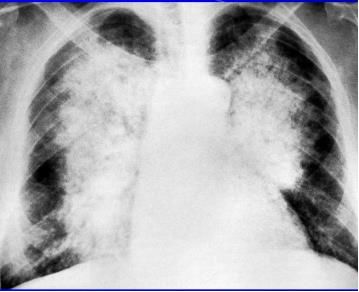

下图是非常典型的蝶翼征。

再来一个更直白的蝶翼征,几乎可以翩翩起舞了。

在现实中,影像学表现如下

典型患者有心脏病,突发气促,咳粉红色泡沫痰,典型影像学如下